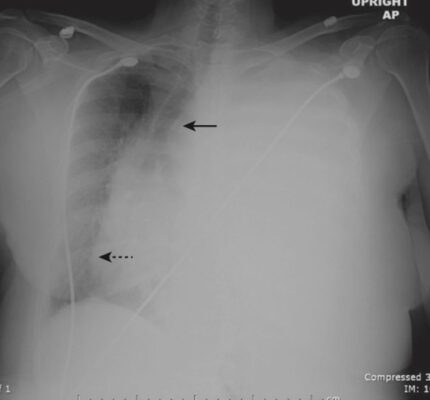

Tràn dịch khu trú (Loculated Effusions)

- Các kết dính trong khoang màng phổi, thường gây ra bởi nhiễm trùng hoặc tràn máu màng phổi cũ, có thể hạn chế khả năng di chuyển bình thường của tràn dịch màng phổi, làm cho tràn dịch vẫn ở cùng một vị trí cho dù bệnh nhân nằm ở tư thế nào.

- Các dấu hiệu hình ảnh học

- Có thể nghi ngờ tràn dịch khu trú khi tràn dịch có hình dạng hoặc vị trí bất thường trong lồng ngực (ví dụ: tràn dịch không ở vị trí thấp của lồng ngực khi bệnh nhân ở tư thế dựng thẳng trên phim chụp X quang thông thường [Hình 13] hoặc nằm ngửa khi chụp CT ngực).

- Xác định vị trí của dịch màng phổi có tầm quan trọng trong điều trị vì các tụ dịch này có xu hướng bị dính, gây khó khăn cho việc dẫn lưu so với các tràn dịch di chuyển tự do.